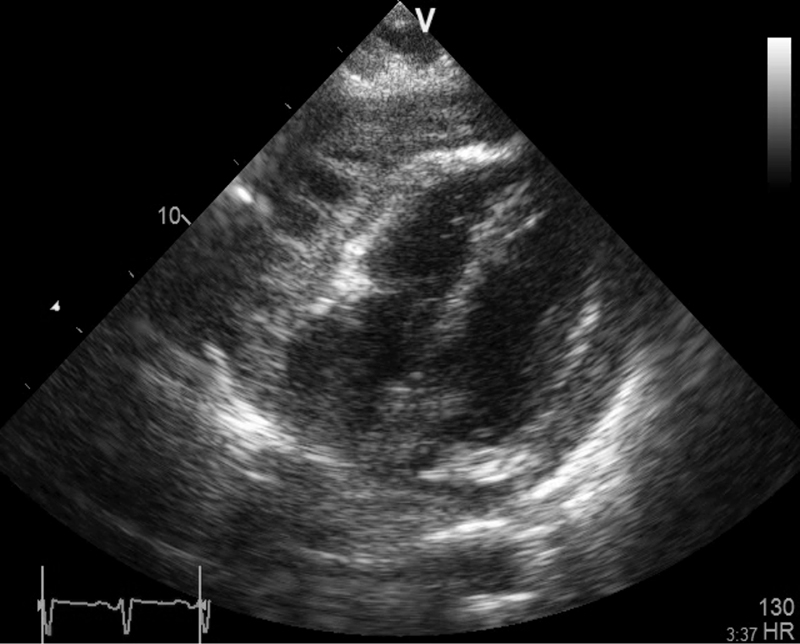

Figure 1: Chest x-ray showing globular cardiac silhouette

Figure 1: Chest x-ray showing globular cardiac silhouette(click to enlarge)

The consultant was struck by the fact that the patient’s heart rate was 110 when lying still in bed and that this increased to 130 when he attempted to sit up. His blood pressure was normal, he looked well, did not appear to have any risks for a pulmonary embolism or an obvious explanation for his tachycardia and markedly elevated D-dimers. His chest X-ray showed clear lung field but he had a rather globular ‘water bottle-shaped’ cardiac silhouette. The ECG revealed widespread T-wave inversion in all leads